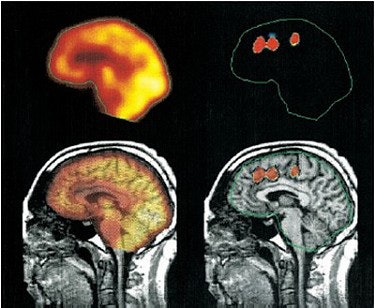

Below, an illustration of activation clusters. Top left, the sagittal averaged PET image of four scans under activation condition. Bottom left is the overlay of an averaged PET image onto the individual MRI dataset. The top right image depicts the identification and delineation of significant activation clusters. The clusters were projected into counter of PET image for better visualization. The same procedure was done for significant deactivation clusters in the bottom right image.

![]() |

| Reprinted by permission of the Society of Nuclear Medicine from: Sabri, O et al. A Truly Simultaneous Combination of Functional Transcranial Doppler Sonography and H215O PET Adds Fundamental New Information on Differences in Cognitive Activation Between Schizophrenics and Healthy Control Subjects. Journal of Nuclear Medicine 2003, Vol. 44, pp. 671-681. |